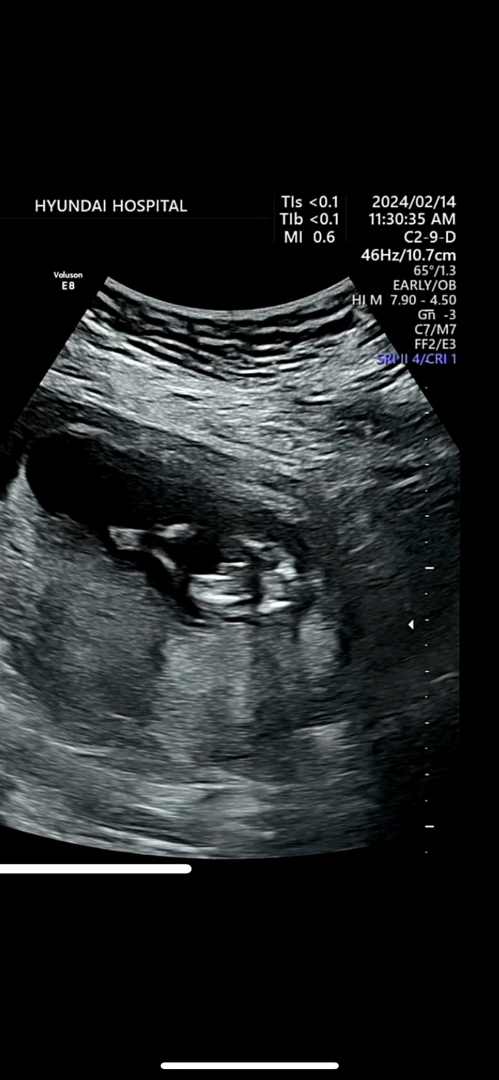

12주차 아들각인가요?

아래에서 위를 바라보고 찍은 모습인데 양쪽다리 사이에 튀어나온게 아들일까요?

오호 12주에 저희 아가랑( 🌶️) 튀어나온 모양이 좀 달라요!!

저희아가는 뾰족한 세모였다면 여기 아가는 삼지창처럼 보여요!

12주에는 아들이던 딸이덩 다 튀어나와있응걸루 알아용..